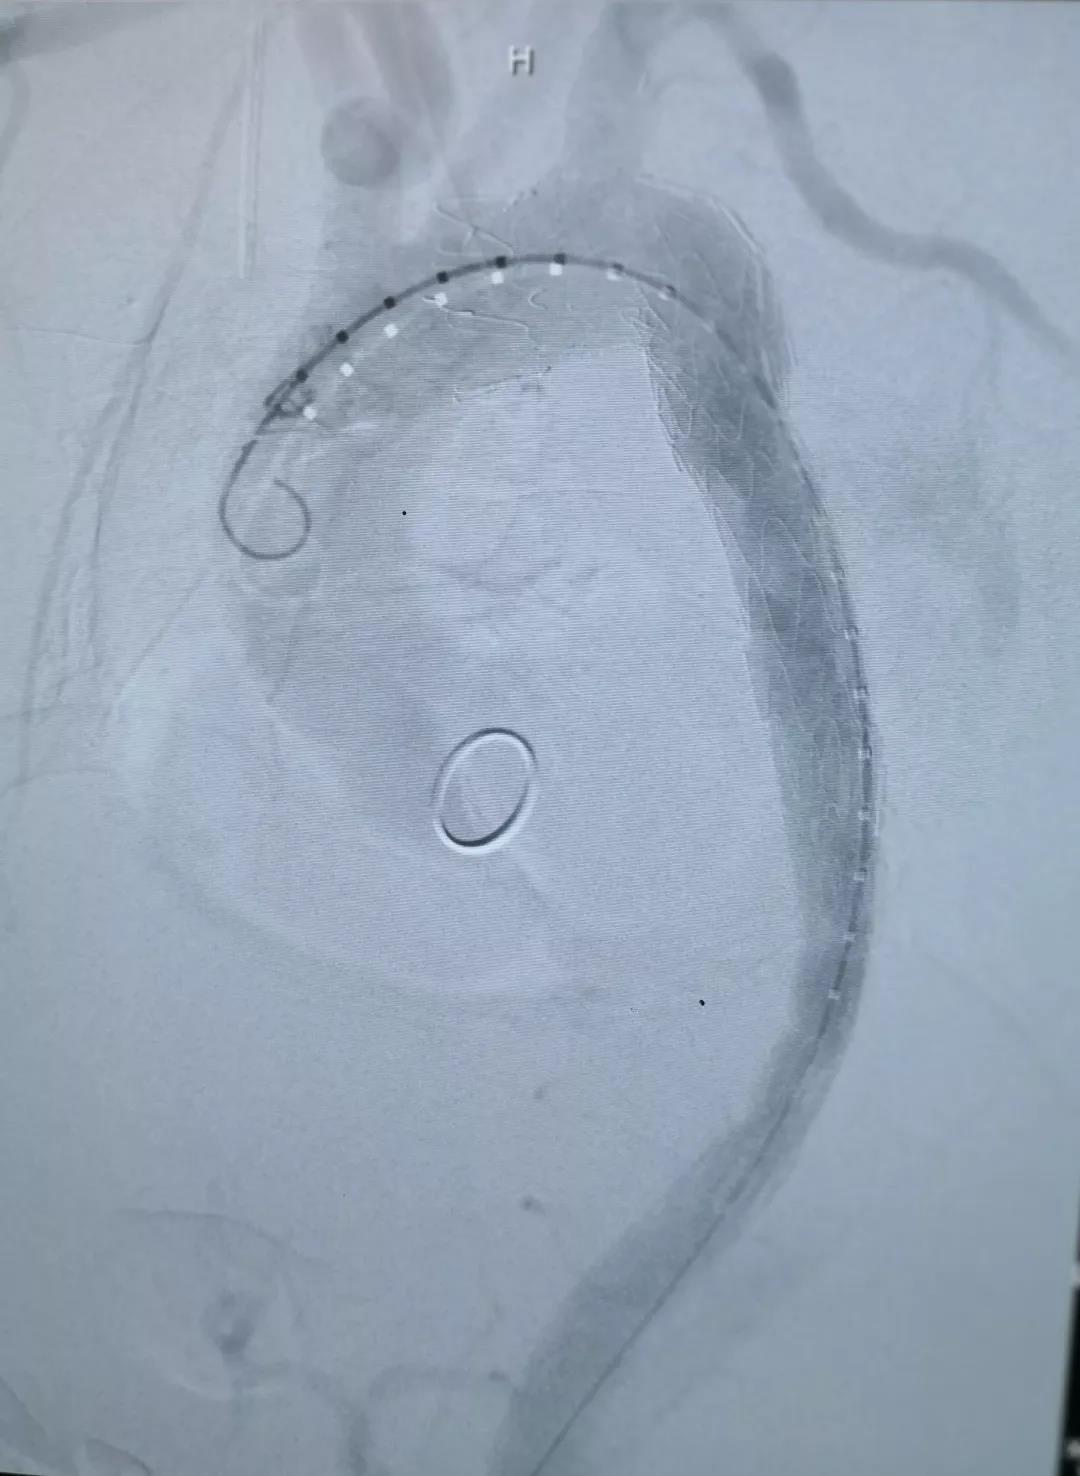

术中通过DSA造影显示:主动脉夹层破口位于左锁骨下动脉近端,真腔压闭。舒畅教授通过左锁骨下动脉预置Longuette™裙边支架,释放 Ankura™ Pro主动脉主体覆膜支架,封堵破口后通过裙边支架显影点准确定位,释放裙边支架,凭借着舒畅教授精湛的手术操作和器械的优异性能,手术过程非常顺利,胸主动脉支架释放良好,患者的主动脉夹层破口封闭良好,左锁骨下动脉释放的裙边支架血流通畅,没有内漏发生。由于患者远端真腔较小,为了保证远端的血流,植入了一个cuff支架,造影显示远端真腔打开良好。

(图:术后造影)

手术结束后的现场提问环节中,舒畅教授在回答关于术式选择的问题时讲到:由于患者破口很大,不适用于体外开窗的方式;且患者左锁骨下动脉相对比较扭曲,与主动脉弓有成角,采用原位开窗的方式比较困难,因此选择了平行支架(即烟囱)的方式进行处理。此病例选择的彩神在线网信彩票-彩神通免费版下载-彩神8争霸vlll-彩神购彩购彩大厅-彩神软件陆立根免费版-彩神ll争霸3-彩神ll彩神8-彩神ll争霸彩票-拼搏在线彩神网网页版Longuette™裙边支架,其独特的外柔内刚的设计,可巧妙的解决烟囱技术中的内漏问题。同时,舒畅教授还提到,Longuette™裙边支架共有4个显影点,DSA下显影良好,可确保术中精准定位。同时,Longuette™支架的内层结构相对裙边适度加长,适宜的长度可在防止大支架将分支支架遮蔽的同时保证分支支架不遮挡左颈总动脉。彩神在线网信彩票-彩神通免费版下载-彩神8争霸vlll-彩神购彩购彩大厅-彩神软件陆立根免费版-彩神ll争霸3-彩神ll彩神8-彩神ll争霸彩票-拼搏在线彩神网网页版新型主动脉支架系统在防堵、防漏、防疲劳方面都进行了周全的考虑,是主动脉疾病的腔内治疗在主动脉弓部方向上的创造性突破。